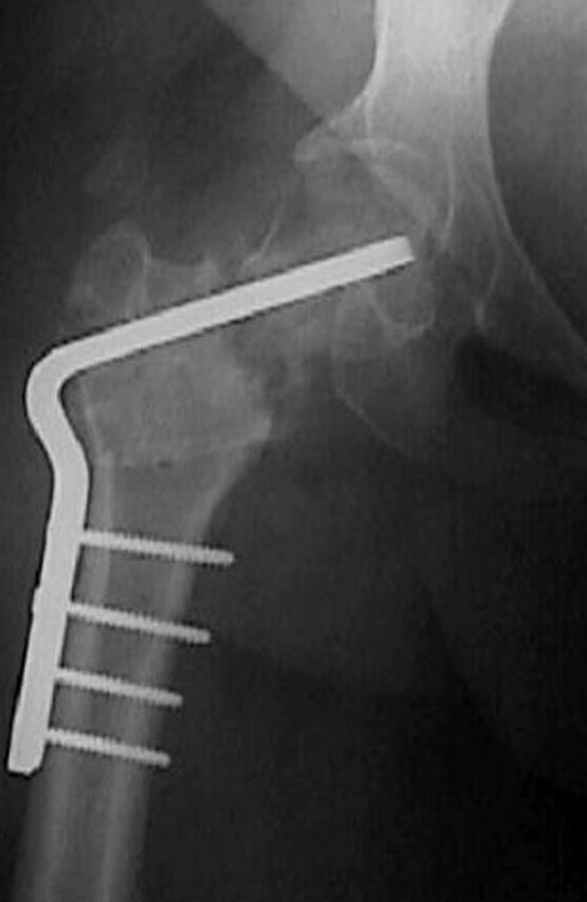

Несколько снимков из моей коллекции, чтобы разьяснить, почему мы до сих пор делаем различные варианты остеотомии.

N3 рисунок окончательный снимок, после операции моя рентгенограмма должен выглядеть примерно как эта картина. На N4 снимке клин перед удалением; N5 послеоперации 3 нед.; N6 окончательная рентгенограмма.

варус при проксимальном отделе 95 градусной пластиной.